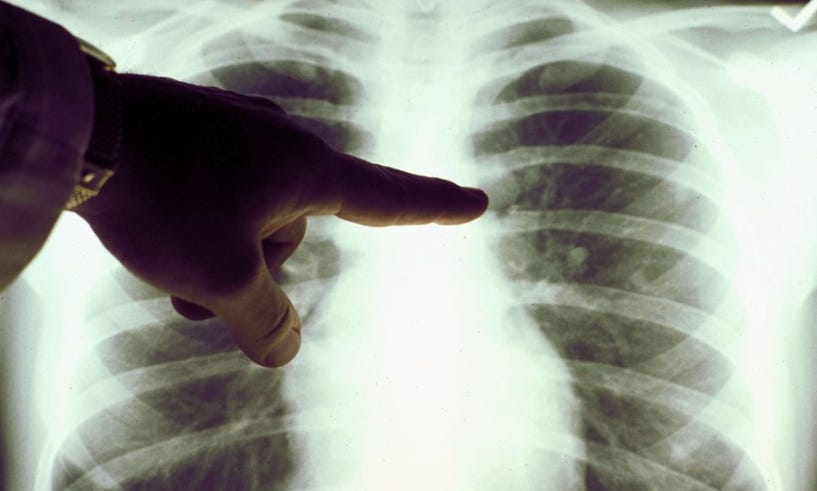

The case study of bones is pretty interesting, and weird. This is an old story and was originally covered by Wired but has been picked up again this week.

A doctor can’t tell if somebody is Black, Asian, or white, just by looking at their X-rays. But a computer can, according to a surprising new paper by an international team of scientists, including researchers at the Massachusetts Institute of Technology and Harvard Medical School.